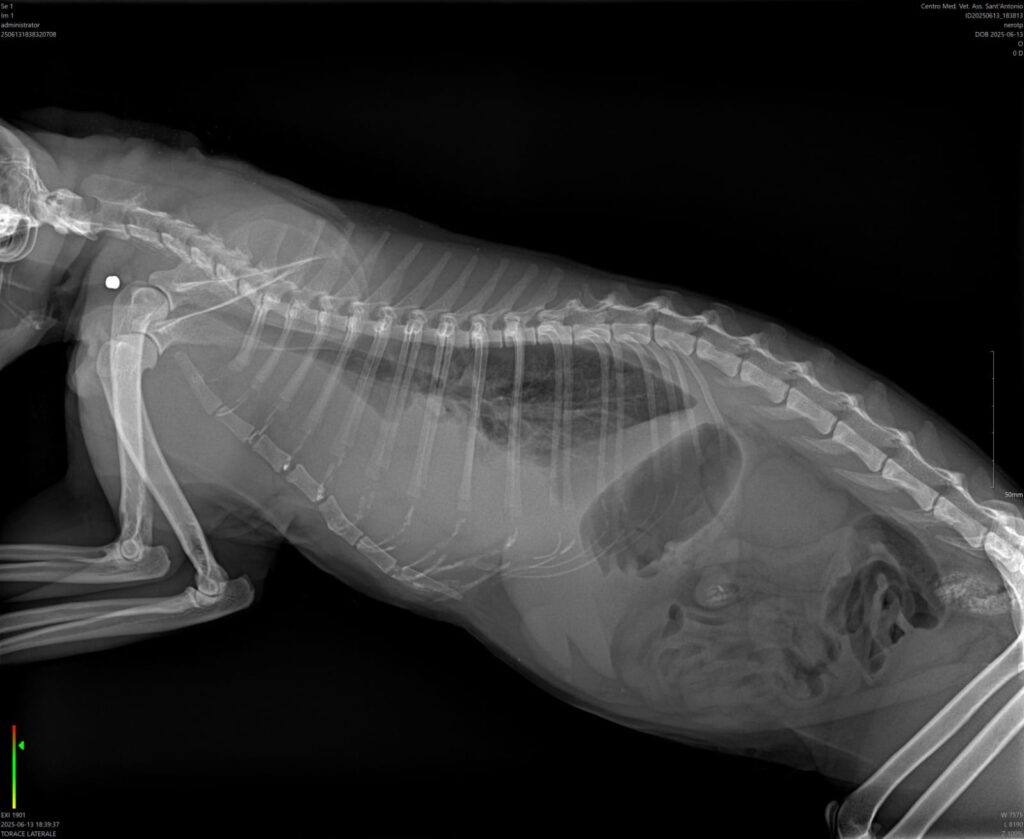

Qualche giorno fa una notizia straziante è giunta ai volontari Oipa di Trapani: un gatto gravemente malato e con difficoltà respiratorie si trovava agonizzante per strada. Il micio è stato prontamente recuperato e trasferito presso una Clinica Veterinaria convenzionata con il Comune. Alla visita medica è stato riscontrato qualcosa di agghiacciante: il gatto è stato sparato qualche giorno prima e alle radiografie si evidenziano dei proiettili che gli hanno perforato la guancia e il torace, causando delle lesioni mortali.